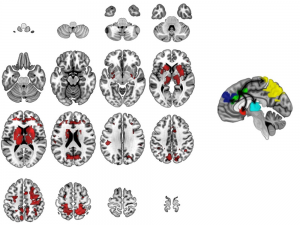

In children with OCD, the brain’s arousal center, the anterior cingulate cortex, is ‘hijacked.’ This causes critical brain networks to stop working properly. Image adapted from Diwadkar VA, Burgess A, Hong E, Rix C, Arnold PD, Hanna GL, Rosenberg DR. Dysfunctional activation and brain network profiles in youth with Obsessive-Compulsive Disorder: A focus on the dorsal anterior cingulate during working memory. Frontiers in Human Neuroscience. 2015; 9: 1-11., CC BY-SA

Through sophisticated, high-field brain imaging techniques – such as fMRI and magnetic resonance spectroscopy – that have become available recently, we can actually measure the child brain to see malfunctioning areas.

We have found, for example, that children 8 to 19 years old with OCD never get the “all clear signal” from a part of the brain called the anterior cingulate cortex. This signal is essential to feeling safe and secure. That’s why, for example, people with OCD may continue checking that the door is locked or repeatedly wash their hands. They have striking brain abnormalities that appear to normalize with effective treatment.

We have also begun a pilot study with a pair of identical twins. One has OCD and the other does not. We found brain abnormalities in the affected twin, but not in the unaffected twin. Further study is clearly warranted, but the results fit the pattern we have found in larger studies of children with OCD before and after treatment as compared to children without OCD.